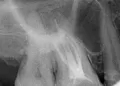

Стоматолог-имплантолог, скуловой имплантолог, хирург, челюстно-лицевой хирург

Стаж: 20 лет

Стоматолог-терапевт, детский стоматолог, пародонтолог, эндодонтист

Стаж: 23 года

Стоматолог-терапевт, детский стоматолог, ортодонт

Стаж: 14 лет